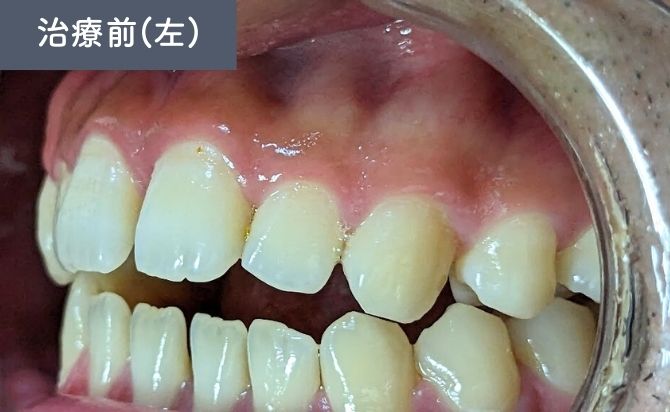

診察では、上顎左右1番間の歯間空隙(すきっ歯)が認められ、審美面での改善希望が強い症例でした。また、前歯部では上下の噛み合わせが接触しない開咬(オープンバイト)の状態が確認されました。

上下前歯には軽度の前突傾向があり、歯列弓の乱れによって歯間空隙と噛み合わせの不安定さが生じている状態でした。

臼歯部の咬合は比較的安定しており、前歯部を中心とした矯正治療で十分な改善が見込める症例と判断しました。

歯並びの変化(左)